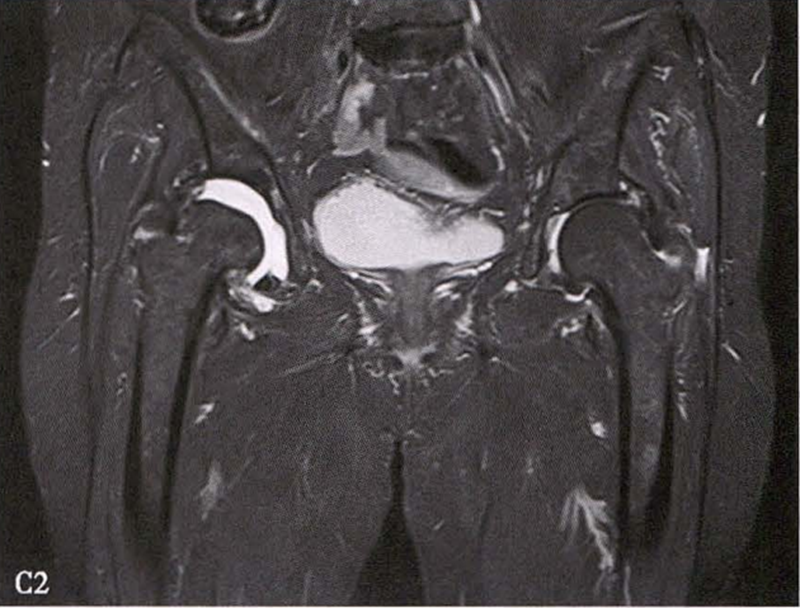

C.女性,89岁,右侧股骨头坏死Ⅳ期。X线片示右侧股骨头压缩变扁,右侧髂臼密度增高,关节内侧间隙狭窄、不均匀(C1)。MRI示右股骨头压缩变扁,右髋关节腔比较多积液(C2)。